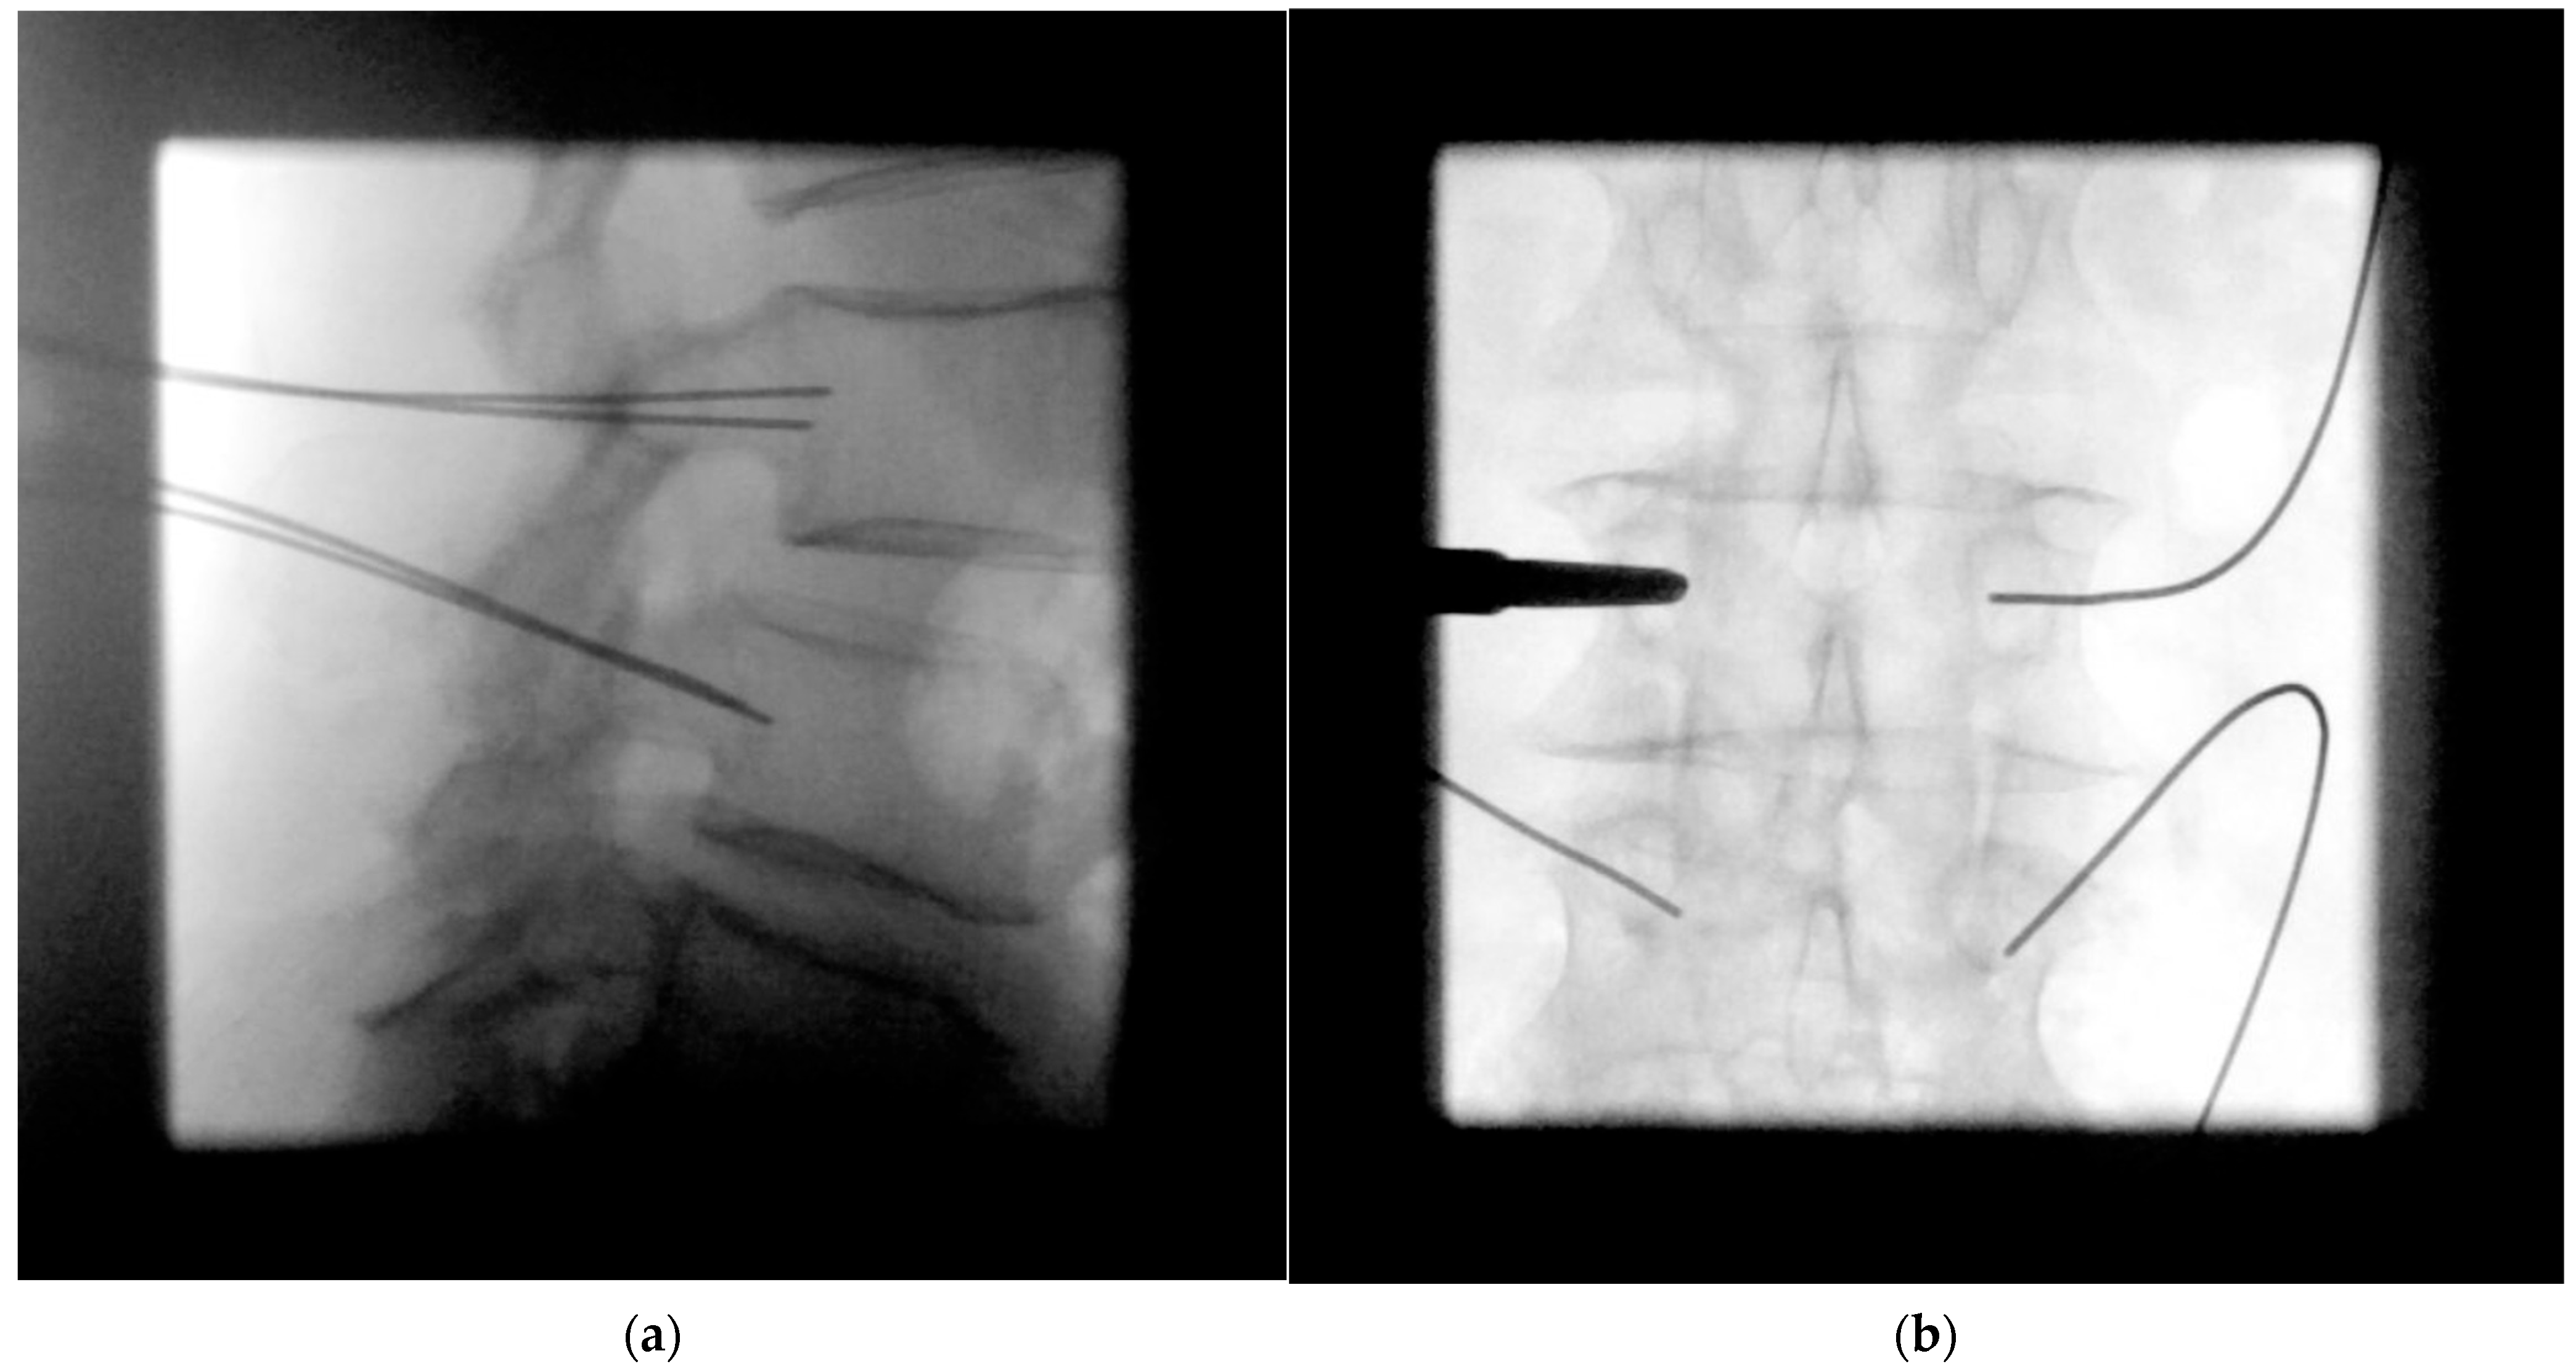

- Pedicle screw insertion

- Cage placement under lateral radiographic control

- MIS rod insertion using haptic feedback and no or very sparse lateral radiographic control